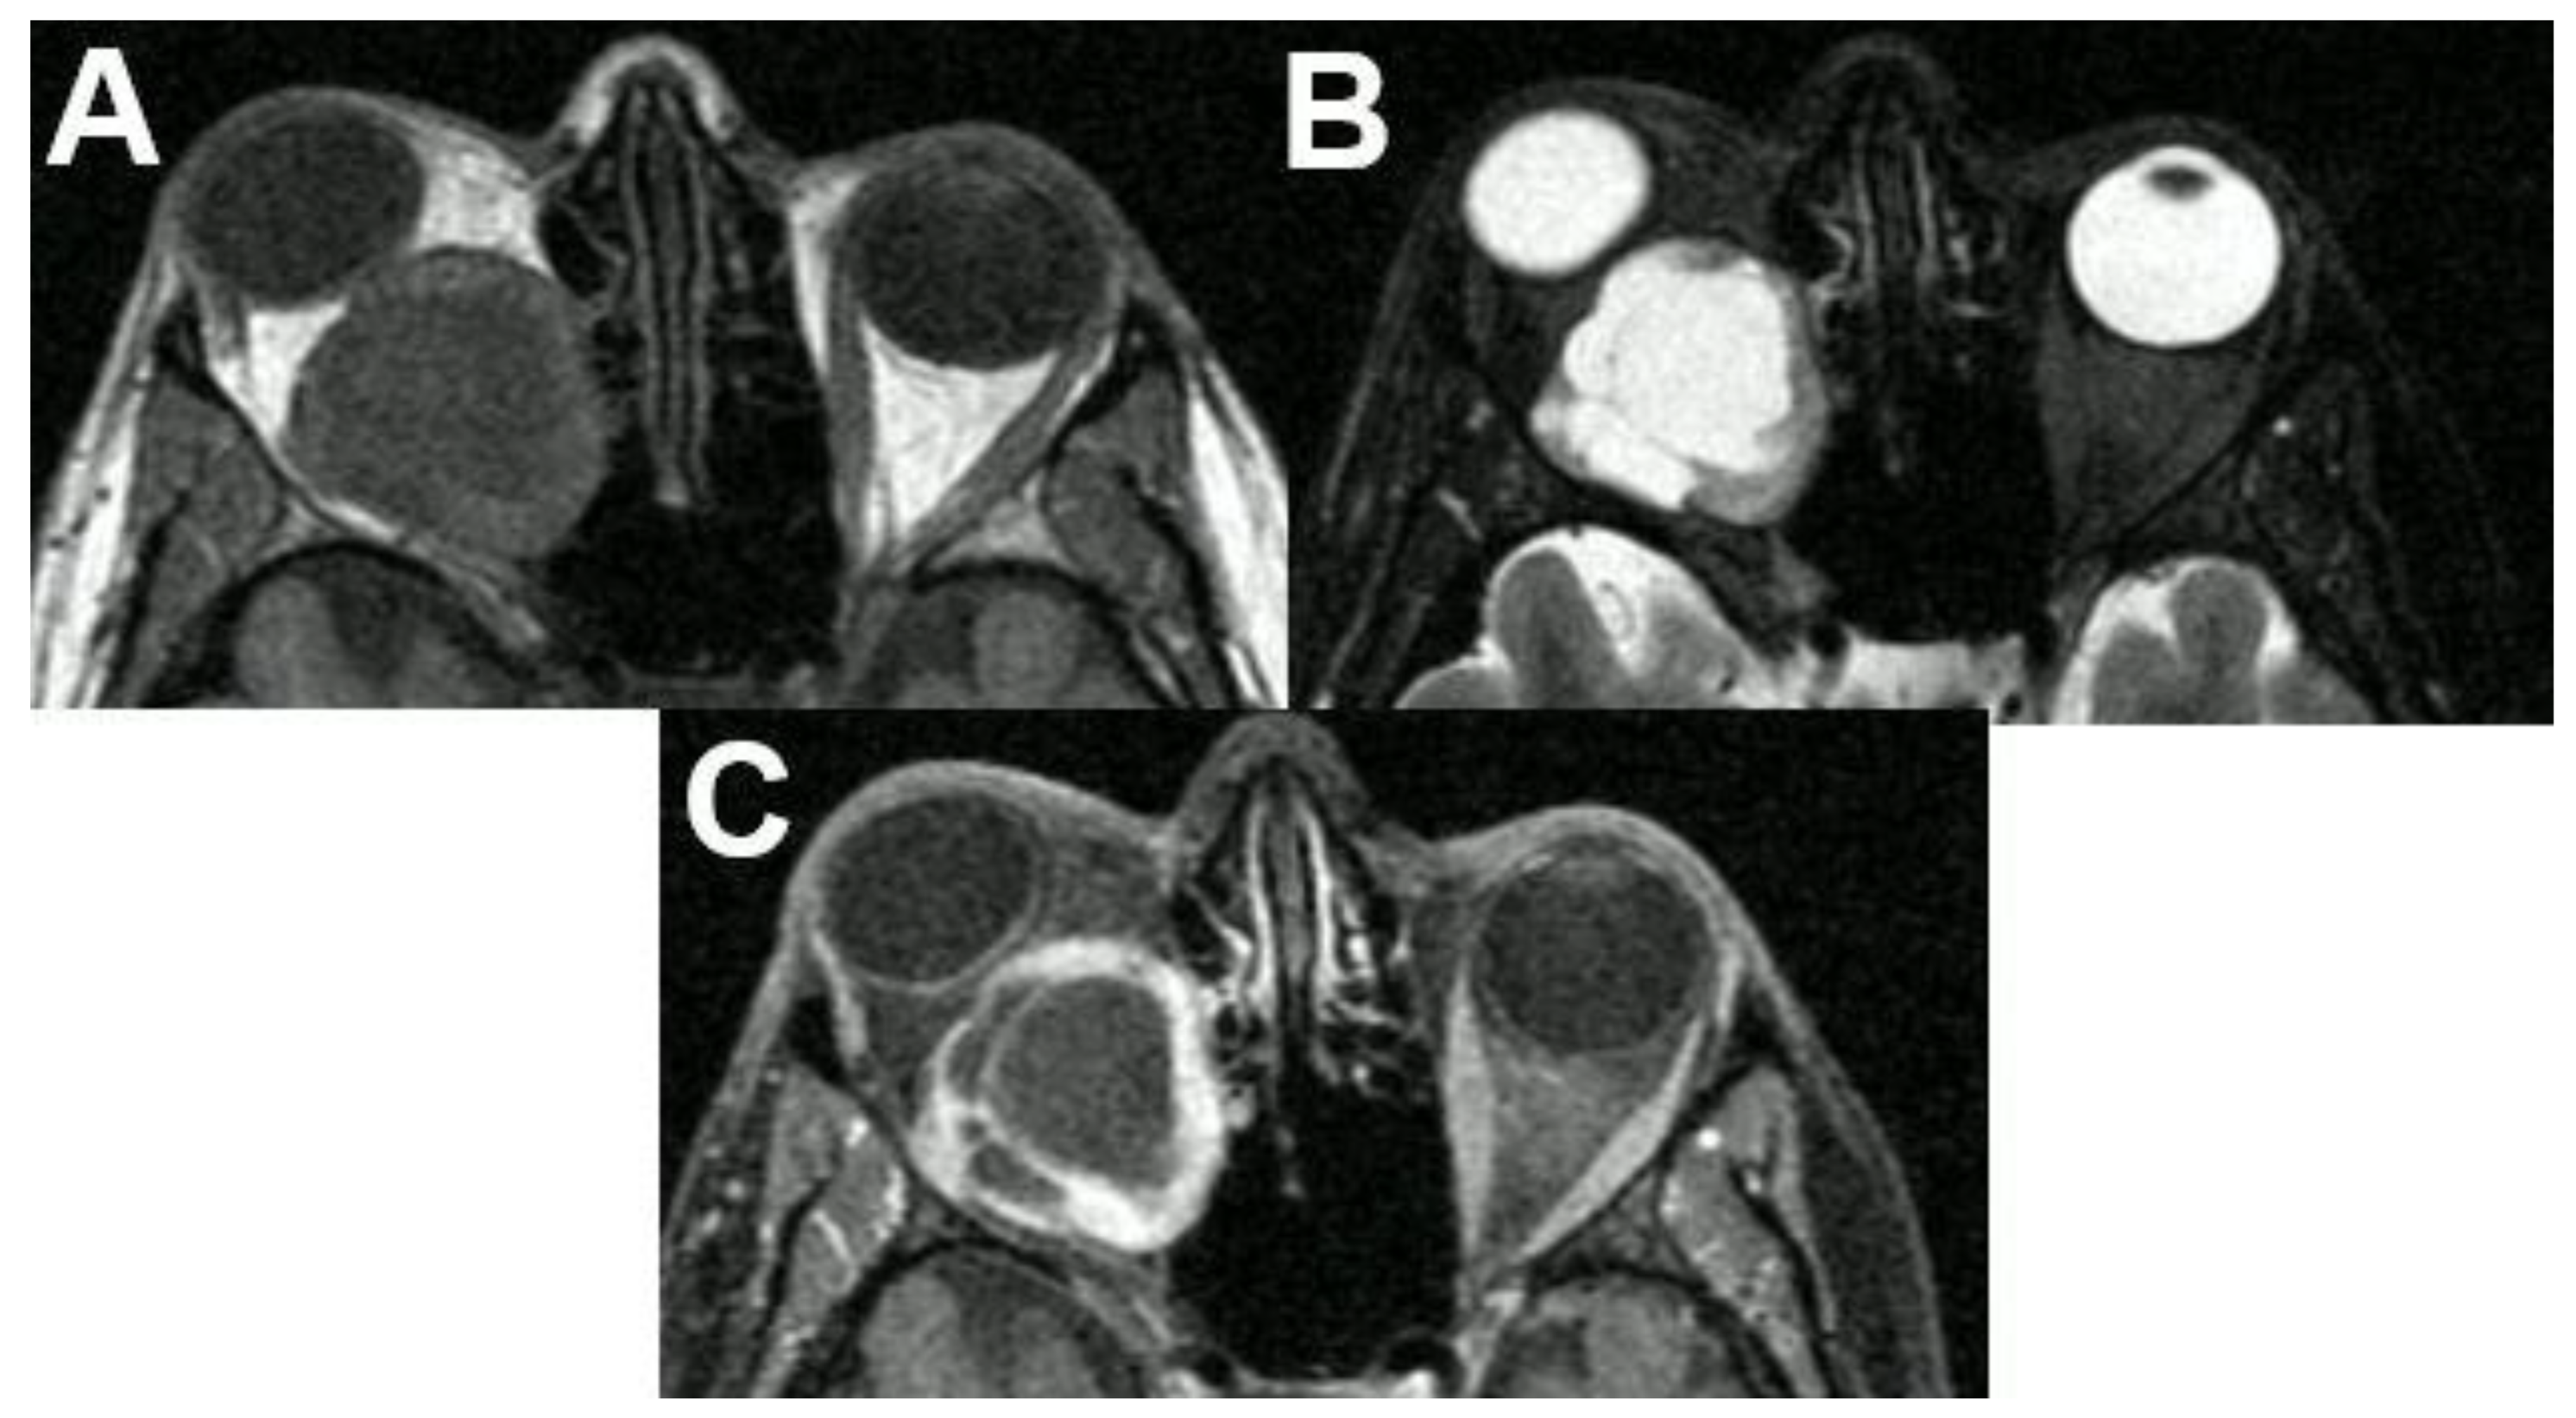

3.1.2. Uveal Melanoma